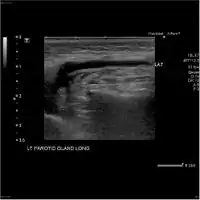

-

Acute left parotid sialadenitis -

Acute left parotid sialadenitis